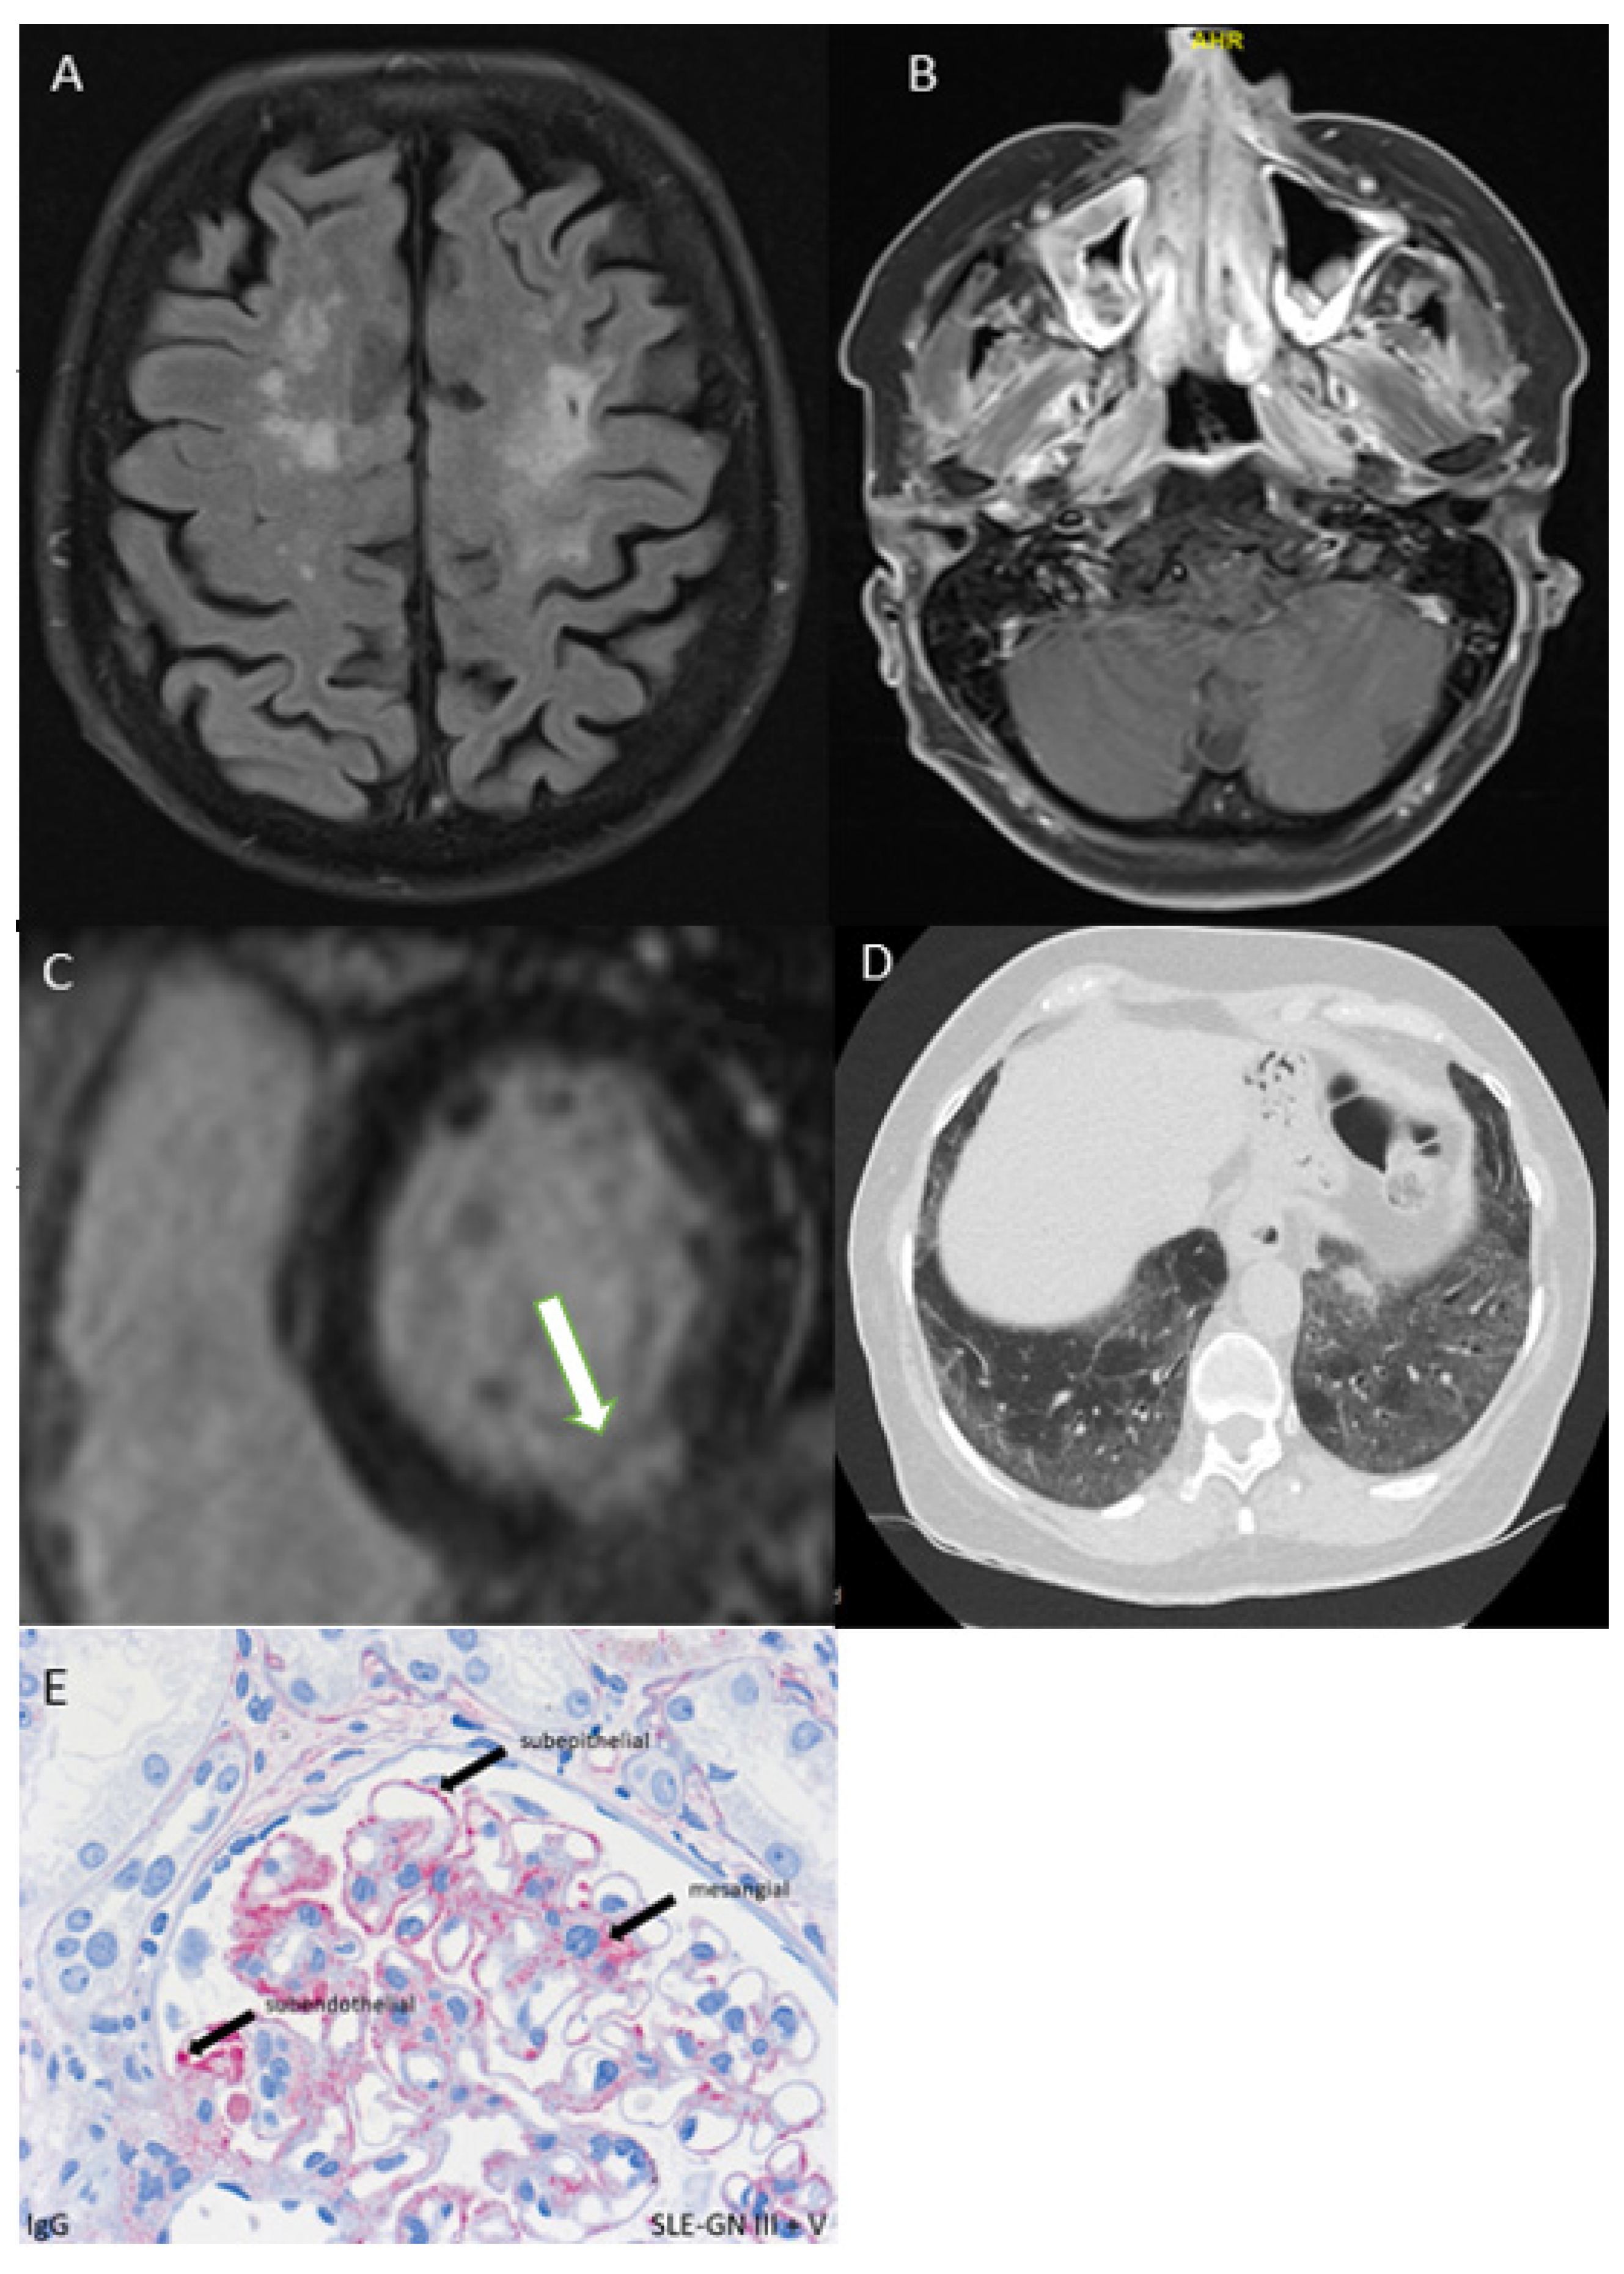

- CNS and PNS: head MRI, neurological examination;

3.5.2. CNS or PNS Involvement